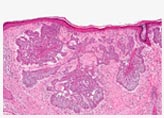

This is a 83 year old female who had a previous skin cancer surgery 1 year ago by another physician. She is seen for a suspicious lesions around her scar. Again, it does not matter if this is a recurrence or in your region. Anything that's changing should be biopsied.

A. Every diagnosis begins with a thorough examination of the skin growth or lesion under a bright light. A biopsy may be taken. This is the most accurate diagnostic test